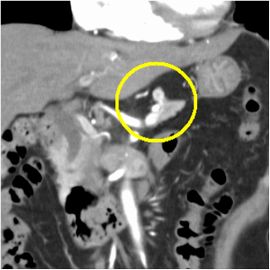

CT検査にて膵体部に腫瘍を認め、精査の結果、膵体部腫瘍疑いと診断し膵体尾部切除術を施行した。

病理診断結果はインスリノーマ(インスリン産生膵島細胞腫)であった。

CT画像